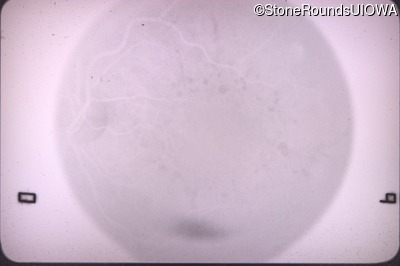

Optical Coherence Tomography - Right - 20/20 -2 sc

Exemplar / OCT Stack